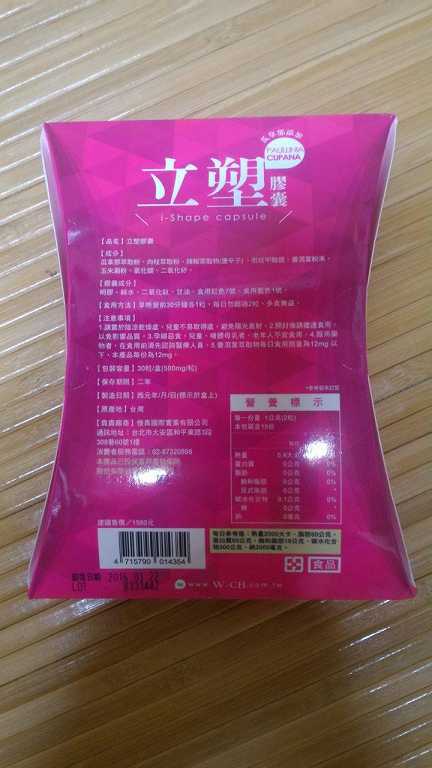

每一盒Supercut塑魔纖立塑膠囊都有三小包,每一小包有10顆膠囊

Supercut塑魔纖立塑膠囊的成分有:瓜拿那萃取粉、肉桂萃取粉、辣椒萃取物(唐辛子)、吡啶甲酸鉻、番瀉葉粉末、玉米澱粉、氧化鎂、二氧化矽。

之前上過相關課程,成分表是依照每項成分的多寡來排列順序,排在最前面的就是產品的主要成分!

食用方式:早晚餐前30分鐘各1粒,每日不超過2粒。(多食無益)

包裝是桃紅色的